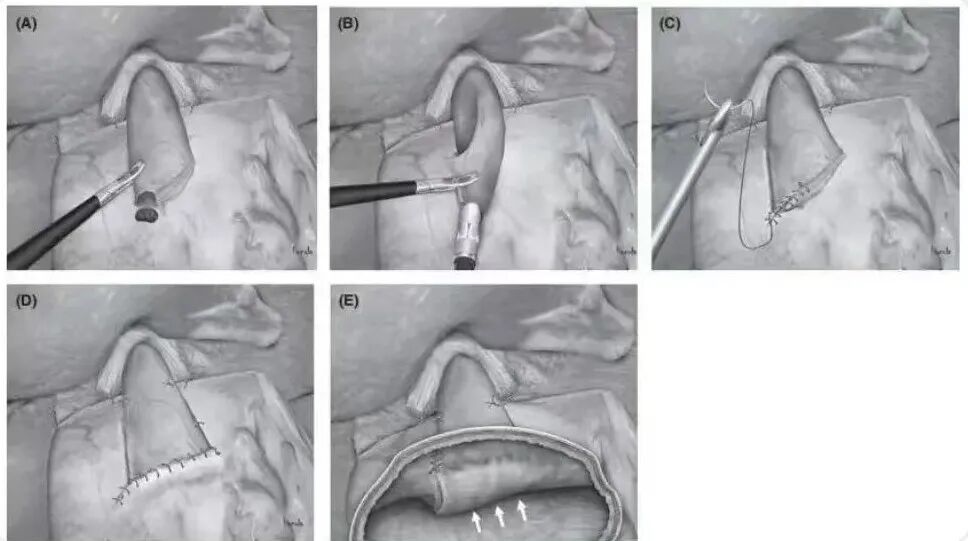

关键手术步骤(如下图):

1.4K腹腔镜下手术视野更加清晰,解剖更加精细,淋巴结清扫更彻底。

2.术中胃镜定位肿瘤边界,肿瘤切除范围达到根治要求、保留部分胃功能;手术安全性高,术后营养状况良好。

3.符合人体生理解剖的消化道重建方式,术后不易发生反流性食管炎、吻合口狭窄等并发症。